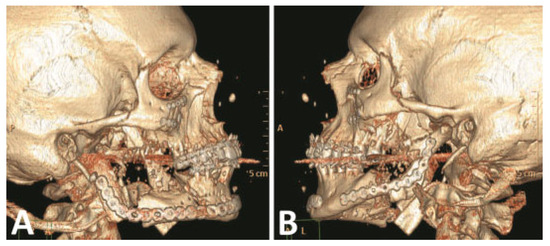

Figure 5.

(A,B) Primary fracture reconstruction; comminuted right condyle debridement and reconstructed with immediate costochondral graft. (Images are courtesy of Colonel Robert Hale.).

Patient 2 returned to the operating room 2.5 weeks post- injury for open reduction internal fixation of the mandibular fractures through a neck incision. The comminuted right ramus and condyle fractures were deemed nonrepairable. After debridement of the comminuted fractures, the right ramus and condyle area was reconstructed with an immediate costochondral graft and a 2.4-mm reconstruction plate.

The comminuted left condyle and body fractures were re- paired with 2.0-mm reconstruction plates (Figure 5). A right cheek wound was closed in layers after debridement and placement of a drain.